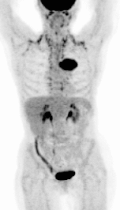

PET — Maximum Intensity Projection Animation

Rotating maximum intensity projection (MIP) of PET scan showing metabolic activity throughout thorax

PET Downloaded 2026-03-15

Pet

Fdg Mip

Wikimedia Commons: PET-MIPS-anim.gif